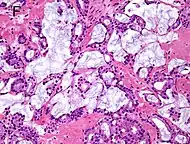

Intraductal carcinoma of the prostate with an infiltrative growth pattern may be morphologically difficult to distinguish from invasive cancer. One focus shows comedonecrosis (arrow), morphologically suggesting Gleason pattern 5 invasive carcinoma (a haematoxylin and eosin, b CK5/6)[19]

Intraductal carcinoma of the prostate with very patchy basal cells identified by immunohistochemistry. At least some of the glands lacking basal cell immunoreactivity represent intraductal rather than invasive carcinoma (a haematoxylin and eosin, b CK 5/6)[19]

Intraductal carcinoma of the prostate gland (IDCP), which is now categorised as a distinct entity by WHO 2016, includes two biologically distinct diseases. IDCP associated with invasive carcinoma (IDCP-inv) generally represents a growth pattern of invasive prostatic adenocarcinoma while the rarely encountered pure IDCP is a precursor of prostate cancer.[19] The diagnostic criterion of nuclear size at least 6 times normal is ambiguous as size could refer to either nuclear area or diameter. If area, then this criterion could be re-defined as nuclear diameter at least three times normal as it is difficult to visually compare area of nuclei.[19] It is also unclear whether IDCP could also include tumors with ductal morphology.[19] There is no consensus whether pure IDCP in needle biopsies should be managed with re-biopsy or radical therapy. A pragmatic approach would be to recommend radical therapy only for extensive pure IDCP that is morphologically unequivocal for high-grade prostate cancer.[19] Active surveillance is not appropriate when low-grade invasive cancer is associated with IDCP, as such patients usually have unsampled high-grade prostatic adenocarcinoma.[19] It is generally recommended that IDCP component of IDCP-inv should be included in tumor extent but not grade.[19] However, there are good arguments in favor of grading IDCP associated with invasive cancer.[19] WHO 2016 recommends that IDCP should not be graded, but it is unclear whether this applies to both pure IDCP and IDCP-inv.[19]